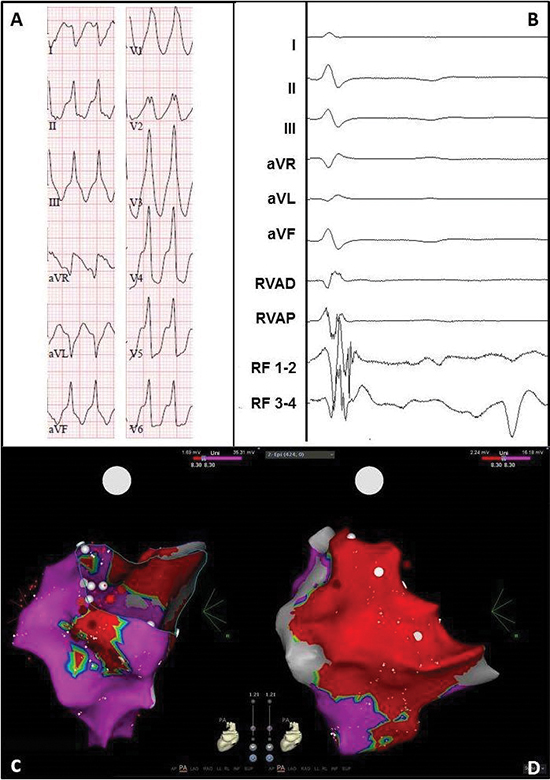

Case 1 : A 70-year-old man suffering from ischemic VTs with recurrent ICD shocks despite use of amiodarone, underwent 3 endocardial VT ablations. Using an activation map, an isthmus was located and targeted in the middle of the inferoposterior to septal area of the left ventricle (LV) (areas 3/4/5/6 according to Josephson[12,13], [Figure 2]). Substrate modification of the inferior LV was performed during the second ablation. Since this neither provided long-term freedom of VT, and because of suspicion for an epicardial origin on ECG (wide QRS, pseudo delta wave, [Figure 3A]), a percutaneous epicardial ablation was proposed. Access to the pericardium with a subxiphoideal puncture failed (dry tap), and per hospital protocol surgical access is not performed in the electrophysiology (EP) lab. Therefore, only an endocardial ablation was conducted. The exits of 2 induced VTs were mapped at areas 7 to 10 (apical low lateral/ inferoposterolateral/anterolateral/lateral basal), where several RF applications were performed. Another VT led to supplemental RF applications at areas 5/6/7 (inferior/inferoposterior/apical low lateral).

In the next days the patient again suffered from sustained VTs and therefore underwent a hybrid VT ablation in the OR, during which an endo- and epicardial ventricular substrate modification (LAVA) was performed (Fig.3B-C-D). A total of 55 applications were performed endocardially in area 5/6/7 (inferior/inferoposterior/apical low lateral), and 19 epicardially. The duration of each application was 30 seconds, the average power 36W and the maximum power 41W. No VT could be induced at the end. The patient was discharged after 3 days in the intensive care unit and 4 days on the regular ward.

Figure 3 Electrocardiogram and electro-anatomical maps of case 1

A. Twelve-lead electrocardiogram showing a ventricular tachycardia (115bpm) with right bundle branch block morphology, right axis and early R-wave transition, suggesting a lateral mid-apical origin in the left ventricle. Pseudo delta wave and wide QRS suggest epicardial origin.

B. Recording obtained in sinus rhythm during the procedure showing local abnormal ventricular activation at the RF catheter. RVAD/P = right ventricular apex distal/proximal, RF = radiofrequency.

C. Inferior view of the bipolar endocardial voltage map showing a low voltage area from inferoposterior to low apical in the lateral wall (area 5/6/7). Red dots = RF applications.

D. Inferior view of the bipolar epicardial voltage map showing a low voltage area consistent with the endocardial

map. Red dots = RF applications.